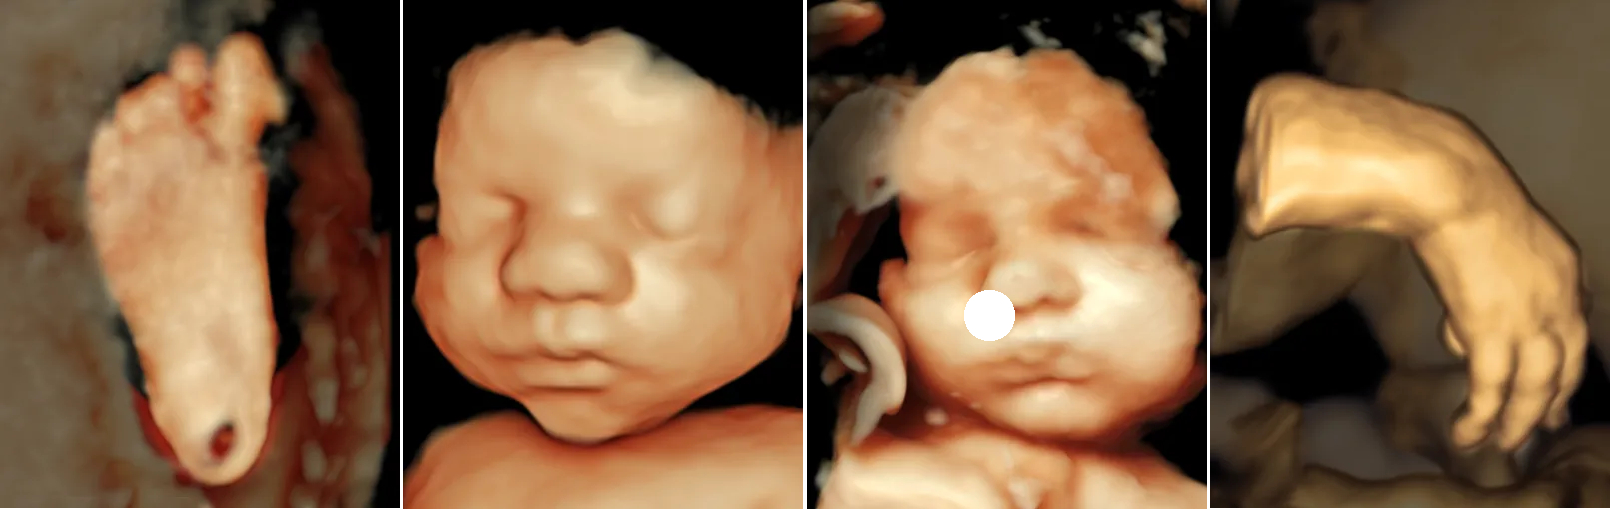

At the Fetal Care and Surgery Center, we perform prenatal ultrasounds using state-of-the-art equipment. This advanced technology allows us to obtain incredibly detailed 2D and 3D images of the smallest structures, examine blood flow, and provide a comprehensive view for patients and their doctors.